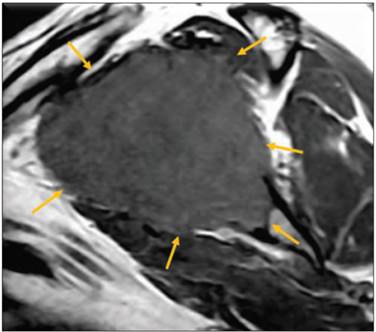

Inició en mayo de 2013 con dolor en hombro izquierdo con limitación a los movimientos de extensión y flexión, se automedicó con analgésicos con lo que mejoró, sin embargo, el dolor se incrementó en el mes de agosto del mismo año por lo cual acudió con un médico ortopedista quien le solicitó RM para descartar lesión de manguito de los rotadores (Figuras 2 y 3).

Figura 2 Resonancia magnética de escápula izquierda en corte sagital, ponderada en T1. Muestra neoplasia lobulada de bordes irregulares que invade la médula ósea (flechas).

En el estudio de RM, la médula ósea de la escápula se observa un tumor lobulado, de contornos irregulares, mal definidos, con zona de transición larga, con patrón permeativo, de comportamiento hipointenso en el T1, iso-hiperintenso en el T2 e hiperintenso en la densidad de protones con saturación grasa. Esta imagen muestra pérdida de la continuidad de la cortical de la cavidad glenoidea hacia su aspecto anterior y se continúa hasta el proceso coracoideo que condiciona desplazamiento anterior e inferior del músculo subescapular, así como desplazamiento superior del tendón del supraespinoso.

El reporte de este estudio fue de imagen sugestiva de neoplasia primaria hacia la escápula izquierda que se continua hasta el proceso coracoides.